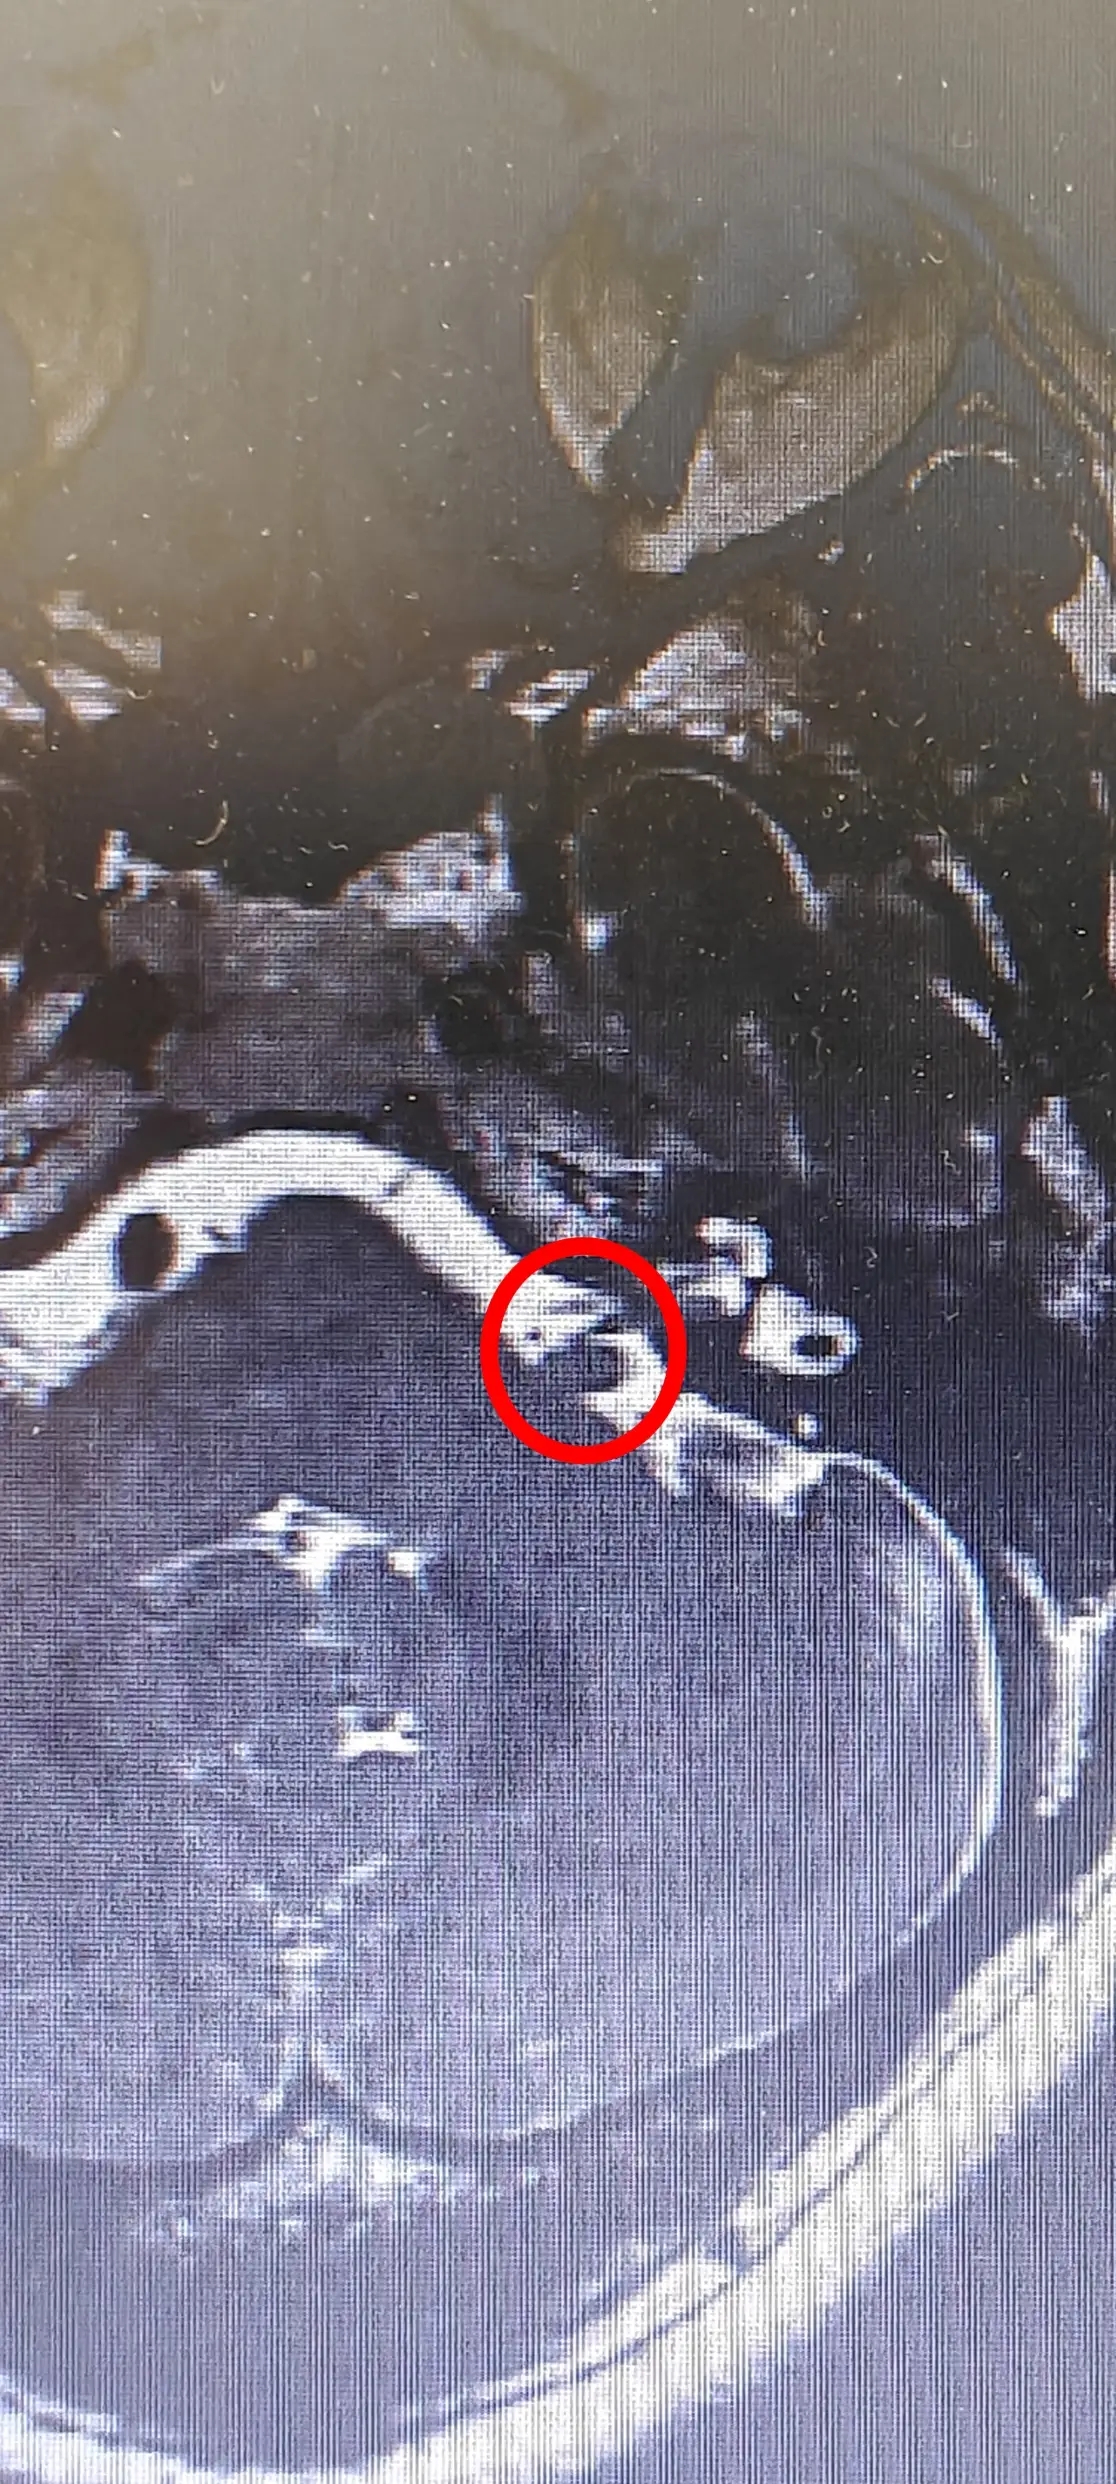

苑玉清主任从事神经外科工作已有 30 余年,结合张阿姨之前的检查报告,经过详细问诊后,苑主任敏锐地判断张阿姨是「听神经压迫」导致的颅鸣而不是简单的耳鸣。为了确诊病情,医院为张阿姨做了影像学检查,头颅 MRI 显示张阿姨确实是左听神经受压。